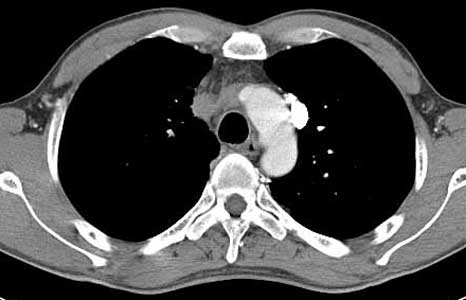

ÀÌÀü¿¡ °áÇÙ °ú°Å·Â ÀÖ´Â ³²ÀÚ 41¼¼·Î CXR ÀÌ»ó ¼Ò°ßÀ¸·Î refer